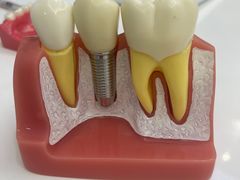

• 牙博士口腔品牌连锁(杨浦店)

• -牙博士口腔品牌连锁(杨浦店)